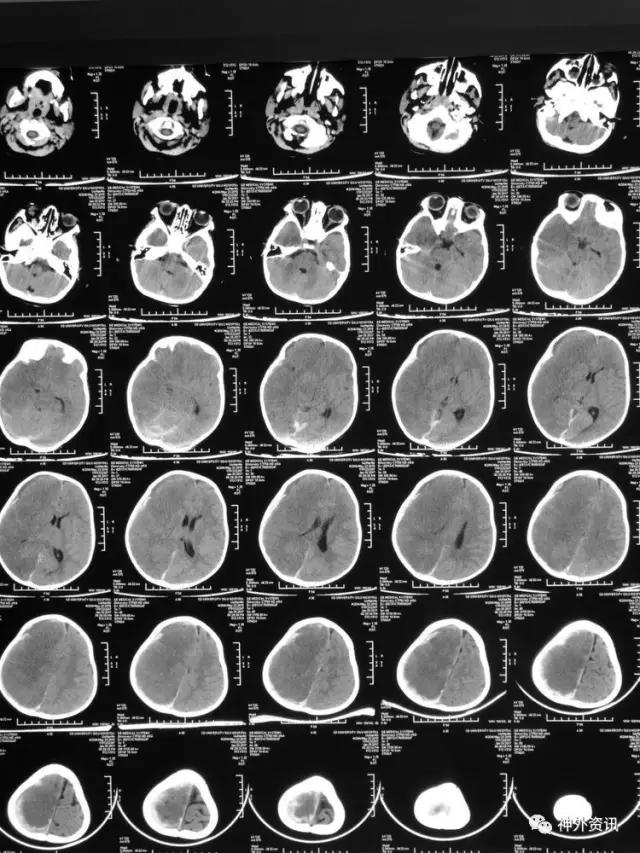

3小时后转至我院急诊科,当时查体:刺痛不睁眼,不发音,刺痛右侧肢体屈曲,右侧瞳孔5mm,对光反应消失,左侧瞳孔0.3cm,对光反应迟钝,立即术前准备并复查CT,结果示右额颞顶枕硬膜下血肿,右侧大脑半球及左侧额叶弥漫性低密度,考虑缺血,中线左移明显,脑沟及环池显示不清:

术后移动CT结果示中线移位较术前减轻,顶枕部蛛网膜下腔出血:

2017.2.1:术后2天复查颅脑CT,结果示中线居中,右侧半球低密度并SAH,左侧半球未见明显异常,左侧脑沟可见显示,双肺少量炎症,不能放松警惕,继续同前治疗。

2017.2.4:术后5天复查颅脑CT,结果示中线居中,左侧半球及环池显示清晰,右侧半球脑沟显示欠清晰,脑组织低密度较前有所好转,继续同前治疗。已加用预消化肠内营养液及促进胃肠动力药物。

2017.2.6:术后7天,复查颅脑CT示情况较前进一步好转,逐步撤掉冰毯,缓慢自然复温。

2017.2.8:术后9天,复查颅脑及胸部CT,结果显示双侧脑沟脑回及环池显示清晰。颅压控制,拔除引流管探头,头部敷料稍加压包扎,此时已更替力月西为丙泊酚,停用呼吸机。